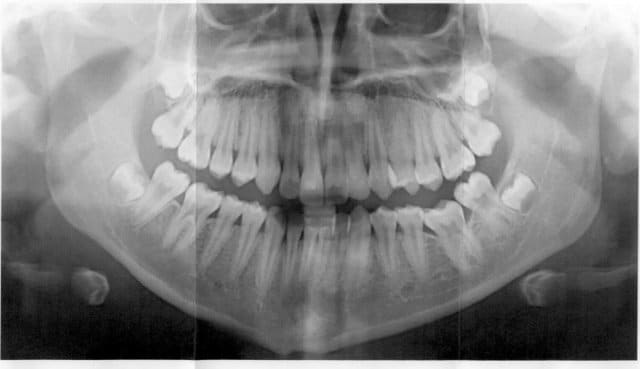

Patiente de 15 ans

La 1° pano est de decembre 2004

La 2° de decembre 2005

Son orthodontiste ne parle que des extractions des 8

peut on egresser 36 ?

Car si je laisse tel quel elle va continuer à ingresser